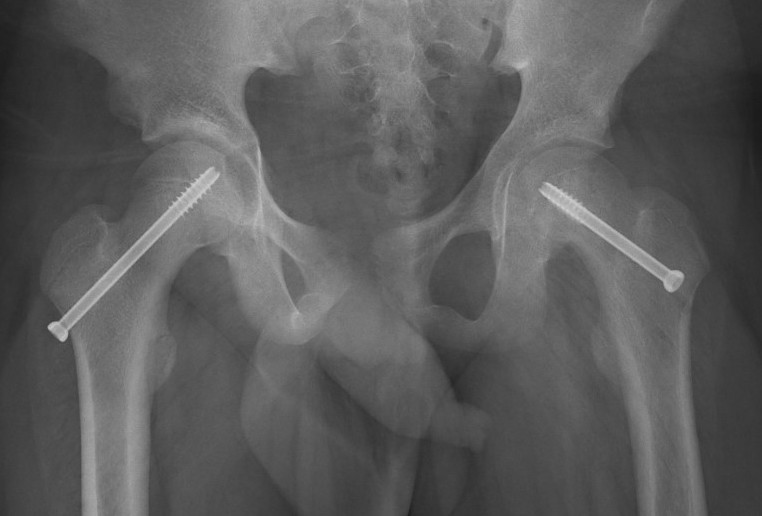

Intertrochanteric / Southwick

Technique

- biplanar

- valgising / flexion / internal rotation

- removal anterolateral bone wedge below LT